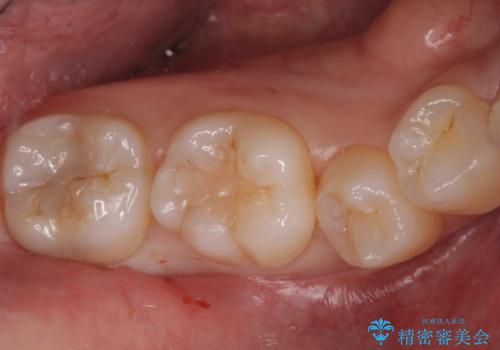

奥歯の深い虫歯

- 以前他院で奥歯にプラスチックの樹脂で虫歯治療を行った患者様です。

かかりつけの歯科医院で虫歯だと指摘され、自費でのゴールドインレーでの修復治療を希望して来院されました。